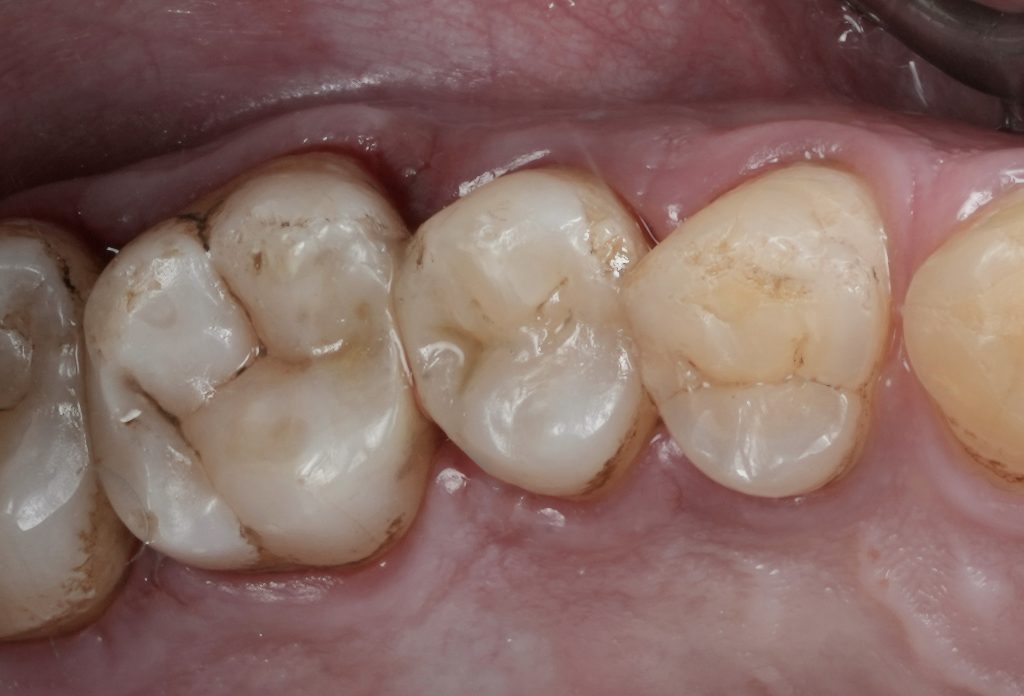

Diagnosis and Case Assessment

Clinical examination revealed a proximal carious lesion affecting a vital posterior tooth. Pulp vitality tests were positive, and no signs of irreversible pulpal pathology were present. Radiographic assessment confirmed caries limited to dentin without pulpal involvement.